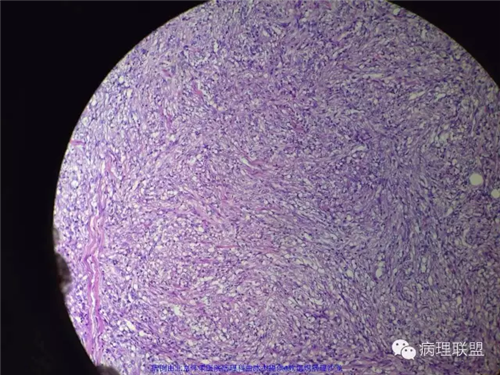

甲状腺肿物,镜下梭形细胞肿瘤,伴坏死及钙化,侵犯横纹肌及涎腺,不知道各位老师考虑什么,免疫组化还没有方向,低分化恶性梭形细胞肿瘤?炎性肌纤维母细胞肿瘤?甲状腺原发还是涎腺原发?谢谢。

好吧 俺也瞎叨叨几句:1,这一例的关键是确定和甲状腺的关系。虽然大体以及描述都说的是甲状腺,但图中没示任何甲状腺。如果找到正常甲状腺组织,当然可以;如果找到其他甲状腺高分化癌的成分,也有提示意义,2,临床表现,80岁,先倾向于UTC了;如果生长再迅速一点,那更支持了。3.镜下,UTC的几个特点(i) widely invasive growth, (ii) extensive tumor necrosis, (iii) marked nuclear pleomorphism, and (iv) high mitotic activity. 此处的坏死,是geographic coagulative necrosis,所以俺才说是有特点。